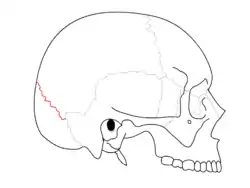

Lambdoid suture (shown in red line) | |

Animation. Lambdoid suture shown in red.